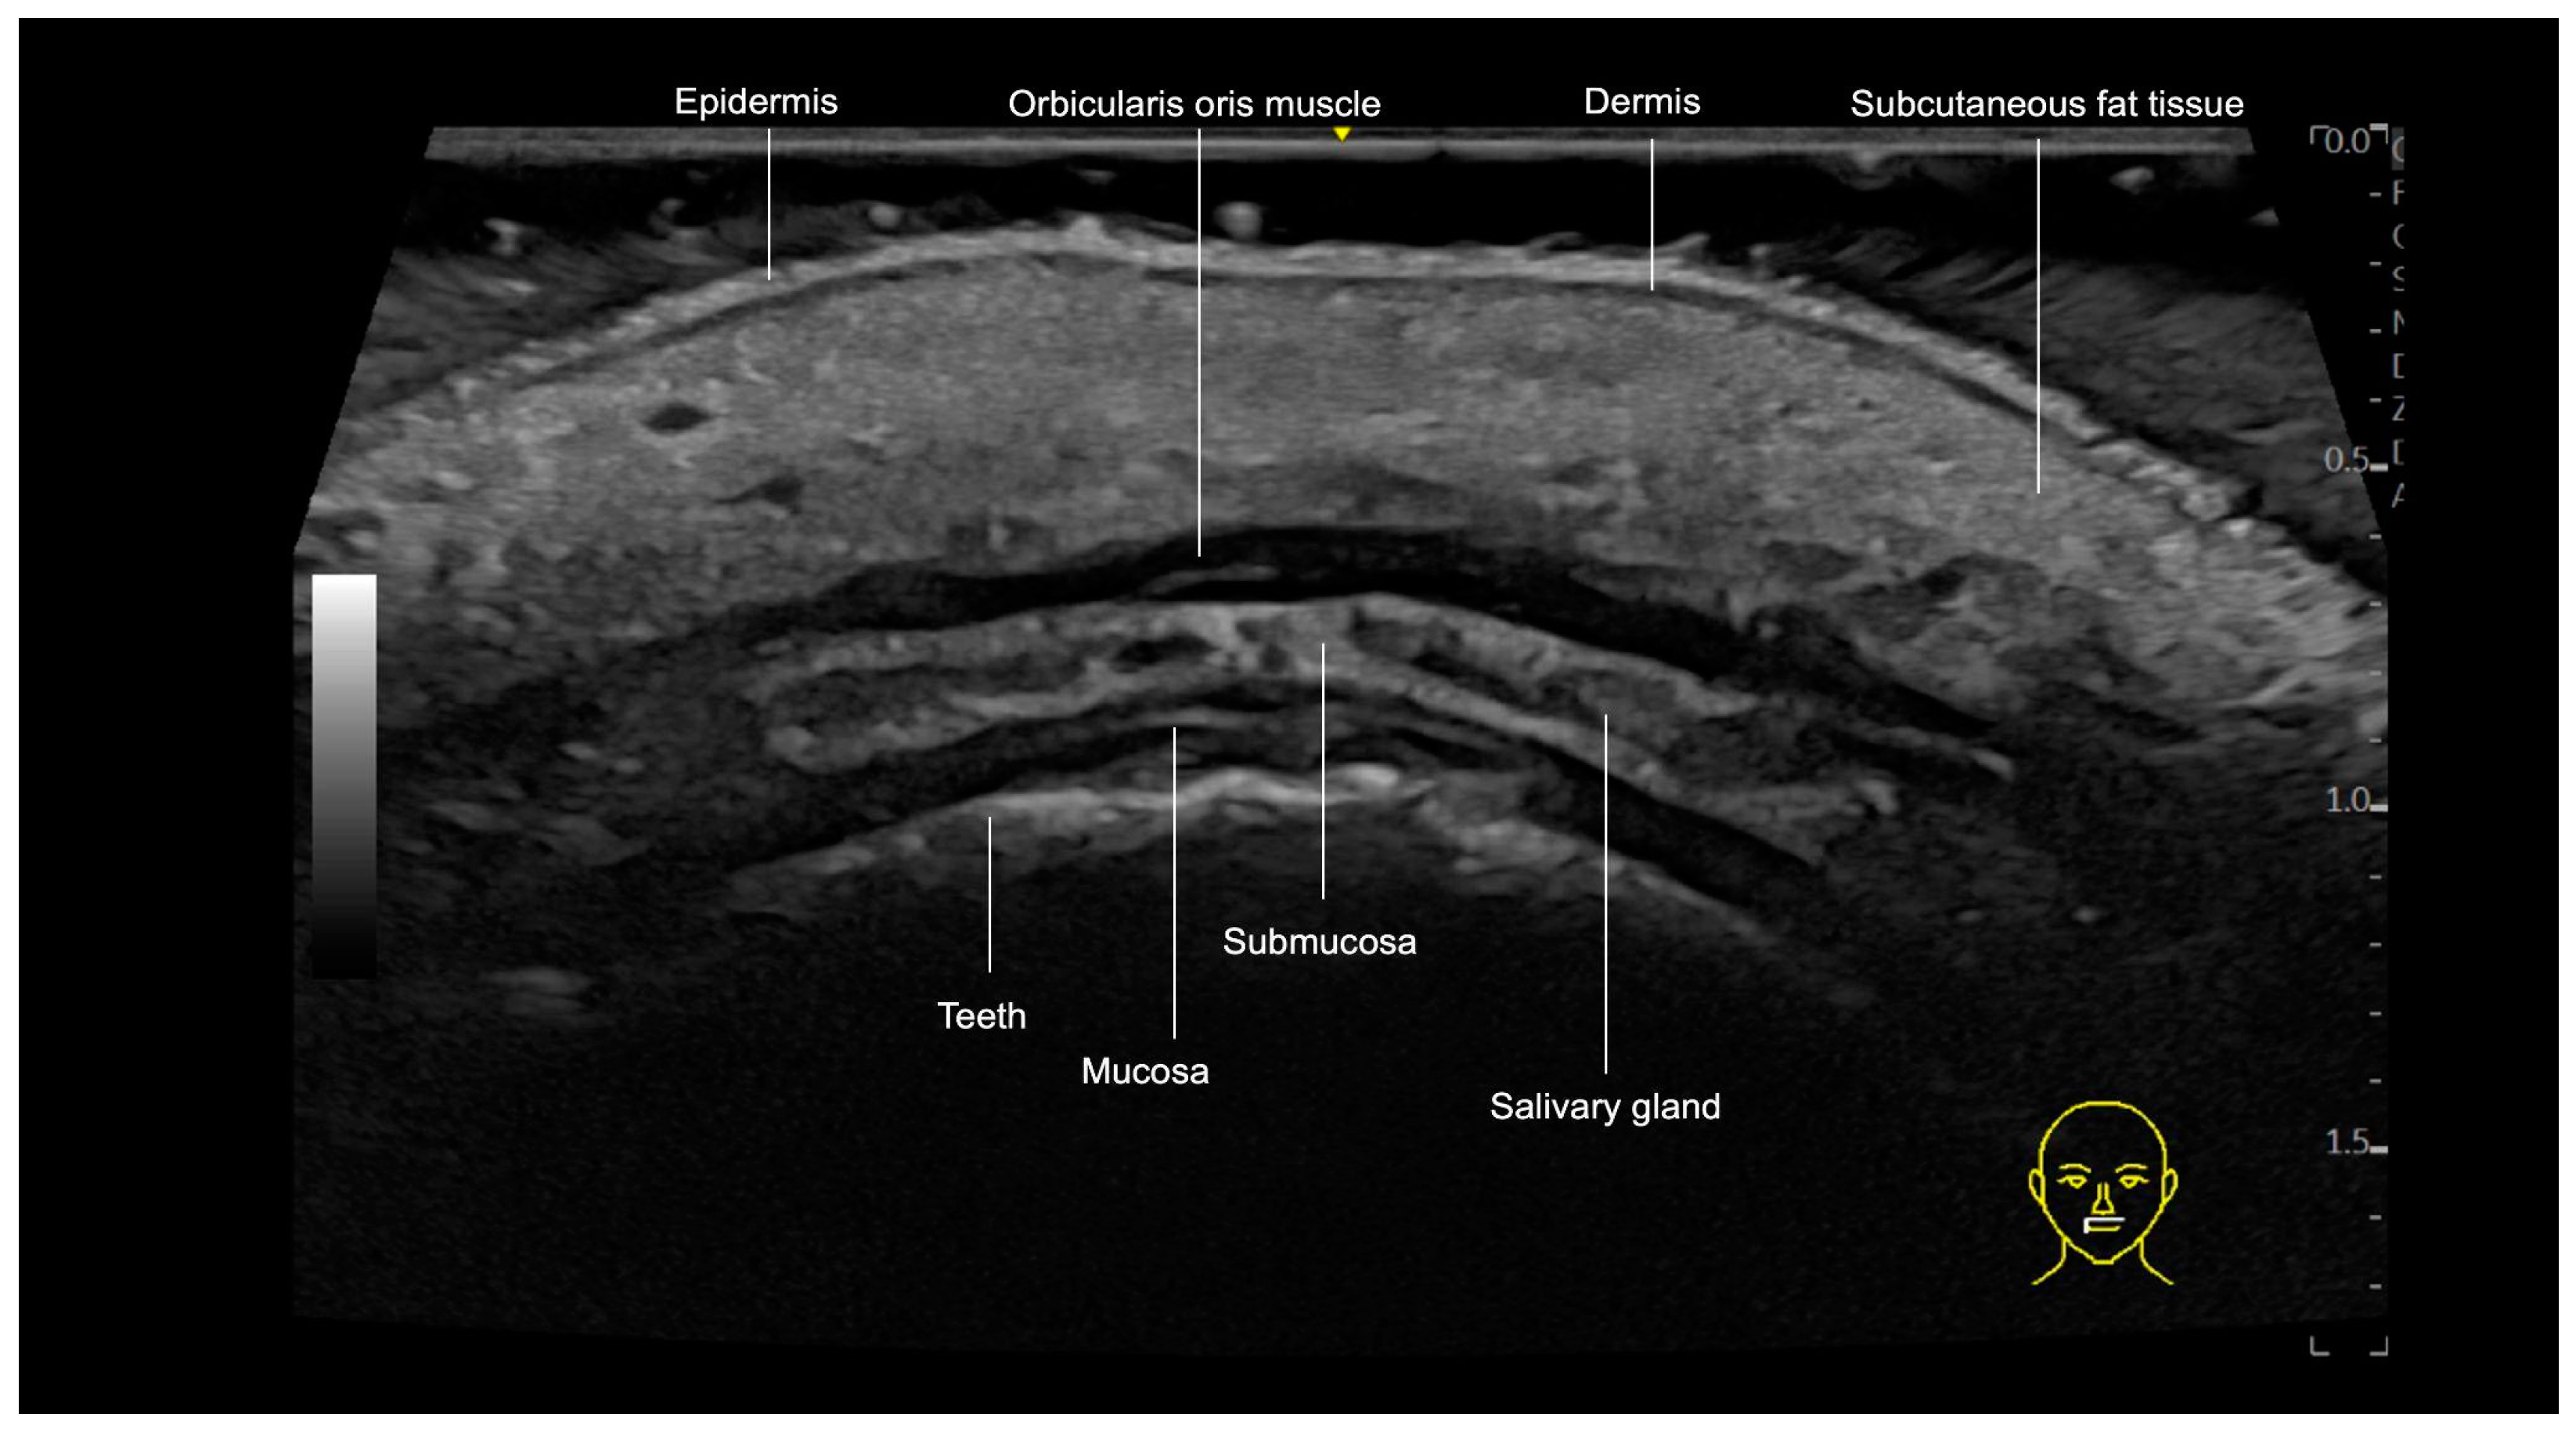

3.3. Lips

3.3.1. Sonographic Anatomy